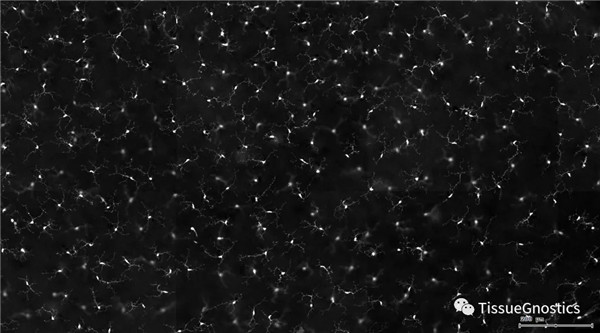

單通道灰階圖(↑:FITC,↓:Texa Red)

根據染色強度,染色面積,細胞形態學,利用正反向回溯功能和設門圈選Gating,排除雜質,細胞碎片,黏連細胞(綠色框線標記),獲得神經元胞體,(粉色框線標記),并將胞體按照面積分為兩類(散點圖)。

由于該視網膜樣本是標記的小膠質細胞,根據面積將神經胞體分為兩類(Small bodycell,Big bodycell),反向回溯Big bodycell中的細胞后,應用Input Gate功能篩選短粗的神經纖維,作為激活態的小膠質細胞。